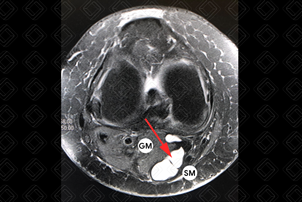

Descrição da figura: Ressonância magnética do joelho, sequência DP evidenciando cisto de Baker (seta vermelha) localizado entre o gastrocnêmio medial (GM) e semimembranoso (SM).

Cisto de Baker: T ambém conhecido como cisto poplíteo, apresenta-se como aumento de volume na região posterior do joelho. Possui uma localização típica nos exames de imagem, entre o ventre medial do músculo gastrocnêmio e o semimembranoso. Em geral, ele ocorre por acúmulo de líquido na bursa do tendão semimembranoso.

• Ressonância magnética do joelho: Na ressonância, por se tratar de uma imagem cística, irá apresentar alto sinal na ponderação T2 e baixo sinal em T1, pela presença de líquido, sem realce após a administração do contraste venoso (figura acima).